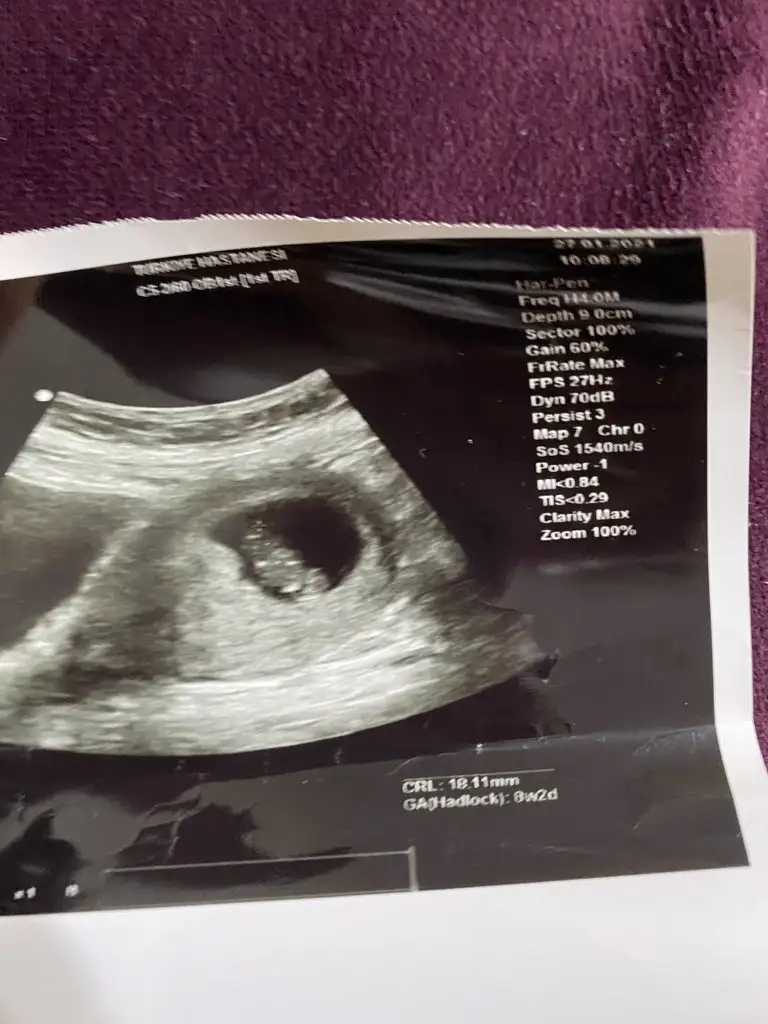

Merhabalar 8+2 de çekilen bu ultrasondan da cinsiyet tahmin edebilecek olan var mıdır